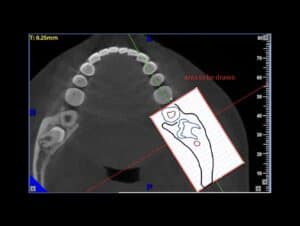

A Cone Beam CT is compiling 3D data, but it still allows us to access it only through 2d representations (slices) in a flat 2D screen. The surgeon has to read these combined 2D images and reconstruct a mental 3D structure of the surgical anatomy, certainly not an easy task to do with precision.

A Challenging surgical case with a complex of vertical and horizontal septa in the posterior sinus. Segmentation of the 3D radiographical and optical data and 3D printing in multiple layers from AMMA Ltd Hong Kong, has allowed for an accurate representation of the anatomy where multiple surgical access approaches were tested.